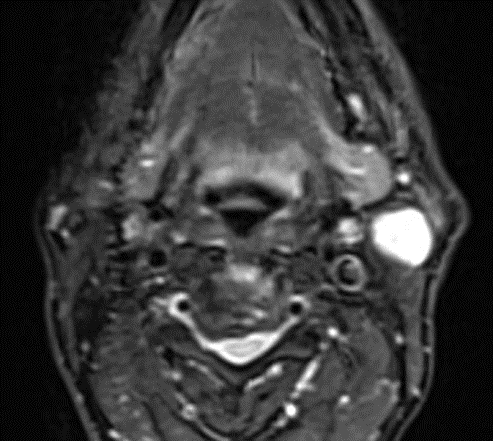

A 69-year-old male noticed a small painless lump in his left parotid region while shaving, Ultrasound examination of the area demonstrated a well-defined lesion measuring approximately 1.7x1.5 cm with internal vascularity, inseparable from the left parotid tail. The rest of the neck ultrasound was unremarkable; MRI was recommended to better define the lesion's origin before histopathological assessment. MRI revealed an oval-shaped, well-defined solid mass lesion in the left parotid gland, measuring about 2.2x1.9x1.3cm in maximum craniocaudally, transverse, and AP dimensions. The lesion is seen as separable from the deep part of the parotid gland, extending posteriorly, abutting the anterior aspect of the related sternomastoid muscle without definite muscle invasion. The lesion eliciting low signal in T1, heterogeneous low signal in T2 weighter images with heterogeneous post contrast enhancement. The main differential diagnoses considered were pleomorphic adenoma and Warthin tumor, although other possibilities could not be totally excluded. Surgical excision was performed. Histopathological analysis revealed Kaposi sarcoma within an intra-parotid lymph node. The lesion was excised with a margin of 0.5 cm. Although the findings were most consistent with a primary nodal Kaposi sarcoma, metastasis from other sites, particularly the skin, should be excluded (Table 1 and Figures 1-4).

Figure 4: MRI Finding of left parotid gland.